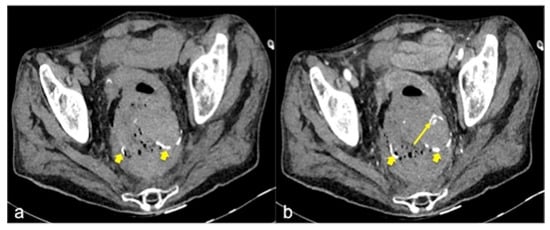

| Diverticulosis (Figure 33) | Asymptomatic or bleeding. | Protruding sacs where the vessels pass through the muscularis layer, between the mesenteric and antimesenteric taenia. |

| Rectal Varices and Haemorrhoids (Figure 35) | Pain and/or bleeding. | Dilated veins with possible bleeding visible in the portal phase; rectal varices are located proximal to the linea dentata while haemorrhoids are located in the anus. |

| Inflammatory Bowel Disease (Figure 39 and Figure 40) | Haematochezia-rectorrhagia. | Acute: thickening of the walls, engorgement of the adjacent vasa recta, hyperaemia of the mucosa and infiltration of perirectal fat. Chronic: the colon and rectum are narrowed and shortened, without haustra, and with proliferation of the perirectal fat. |